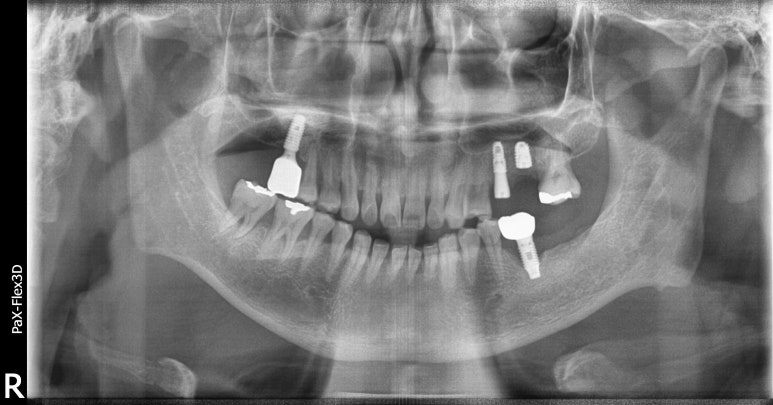

환자분의 첫 내원 시 사진입니다.

거주하고 계시는 동네 치과에서 #25, 26 치아 발치 후 임플란트 치료가 필요하다는 말을 들었는데

저희 디데이치과가 위치한 선릉역 근처에서 근무하고 계셔서 내원해주셨다고 합니다.

우선 살펴보면 임플란트가 필요한 치아는 왼쪽 위 어금니 2개였는데요.

#25 치아는 임플란트를 식립하기에 잇몸뼈의 양이 부족하고 뼈의 상태도 좋지 않아

뼈이식을 진행한 후 잇몸뼈가 단단하게 자리잡힐 때까지 기다렸다가 임플란트를 식립하는

지연식립이 필요한 것으로 진단했습니다.

옆에 있는 #26 치아는 염증이 심해 잇몸뼈가 상당히 녹아 치아 뿌리 일부가 노출되어 있는 상태였습니다.

하루 빨리 발치 후 임플란트를 식립해야 하는 상태였는데,

상악동이라고 하는 공기주머니가 많이 내려와 있어 이를 올려주는 상악동거상술까지 진행해야 하는 것으로 진단했습니다.

뼈이식과 상악동거상술까지 동반한 케이스라 발치한 당일 임플란트 식립은 어려워

일단 내원 당일 발치와 뼈이식까지만 진행하고 약 3개월 후 임플란트 수술 일자를 잡기로 했습니다.